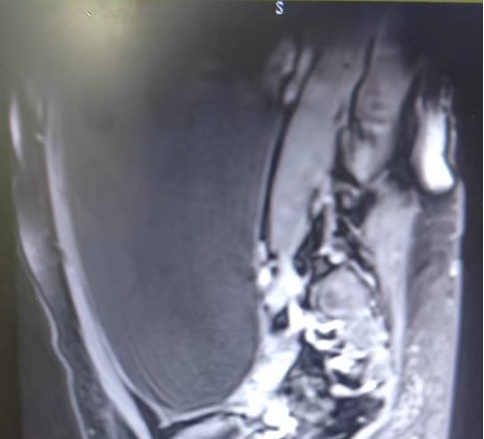

返回上一级 近日,长沙融城医院(原水电八局中心医院)妇科团队成功完成了一例特殊的盆腔巨大包块切除手术,该患者为一名年轻女性,因下腹胀痛、排尿困难等症状前来我院妇科就诊。经过全面且细致的检查,腹部核磁结果显示,其盆腔内竟“藏”着一个直径约30厘米的巨大囊性包块,这一包块严重干扰了患者的日常生活。面对如此棘手的病例,妇科团队在吴昊主任的带领下,经过充分评估,最终决定为该女士实施腹腔镜下盆腔巨大包块切除术。

手术期间,在腹腔镜下,吴主任成功地从包块中抽吸出了约4500ml囊性液体,并顺利将盆腔包块完整切除。术后第二天,该女士便能下床活动,腹部恢复平坦,症状得到明显缓解,生活重回正轨。患者本人及家属对此次诊疗过程感到非常满意,并对我院妇科团队的医疗技术和服务给予了高度评价。